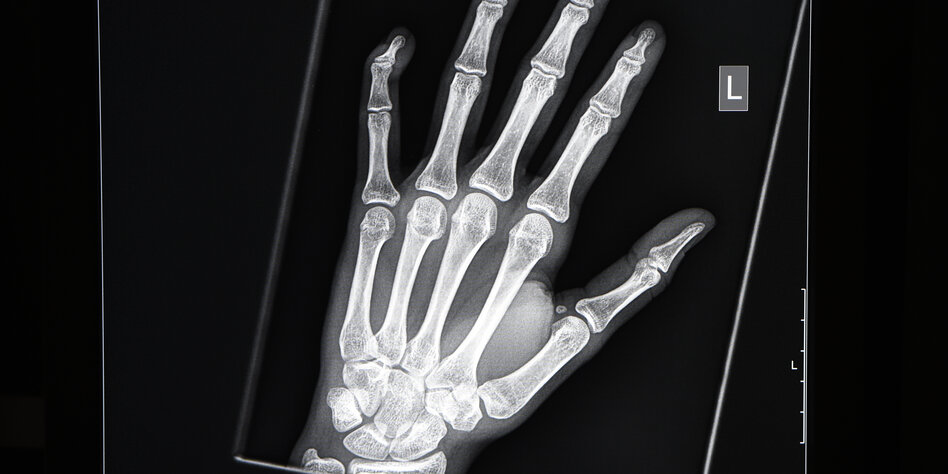

IMG Bild: Röntgenbild von der linken Hand eines jungen Menschen im Alter von 16 bis 19 Jahren

Um das Knochenalter zu bestimmen, wird die linke Hand geröntgt. Die

Radiologen schauen sich die Handwurzelknochen an und untersuchen, in

welchem Entwicklungsstadium sie sich befinden. Bei kleinen Kindern sind

diese Knochen nur Kerne, die dann mit der Zeit wachsen und größer werden.

Dabei schließen sich die sogenannten Wachstumsfugen. Bis zum 19. Lebensjahr

sei dieser Prozess in der Regel abgeschlossen, erklärt Yen. „Danach kann

man keine weiteren Aussagen mehr machen.“ Anders bei den Schlüsselbeinen: